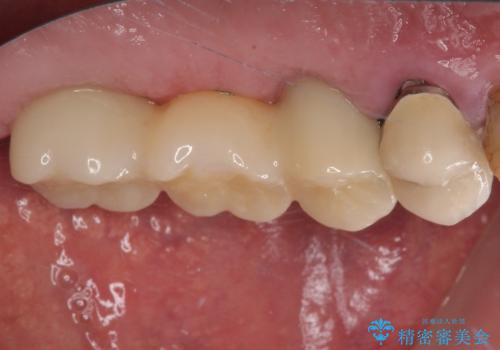

割れてしまった奥歯 抜歯即時埋入インプラントによる短期間治療

いずれの歯も抜歯が必要な状態であり、抜歯即時埋入によるインプラント治療を行うこととしました。

術後にインプラントの安定値を測定し、十分な値が達成された後、速やかにセラミッククラウンにて補綴治療を行うこととしました。